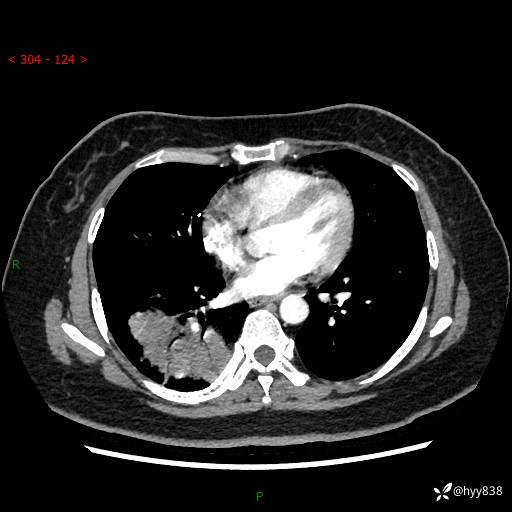

增强动脉期+静脉期